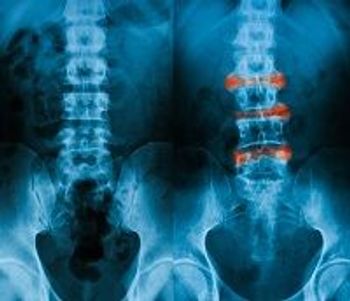

Inflammatory bowel disease patients can be afflicted by various forms of arthritis from peripheral arthritis to ankylosing spondylitis and symmetrical polyarthritis. In this slideshow, we address identification, diagnosis and treatment for these complex cases.